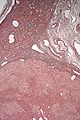

Micrograph of a hepatic adenoma (bottom of image). H&E stain

Hepatic adenomas are, typically, well-circumscribed nodules that consist of sheets of hepatocytes with a bubbly vacuolated cytoplasm. The hepatocytes are on a regular reticulin scaffold and less or equal to three cell thick.

The histologic diagnosis of hepatic adenomas can be aided by reticulin staining. In hepatic adenomas, the reticulin scaffold is preserved and hepatocytes do not form layers of four or more hepatocytes, as is seen in hepatocellular carcinoma.

Cells resemble normal hepatocytes and are traversed by blood vessels but lack portal tracts or central veins.